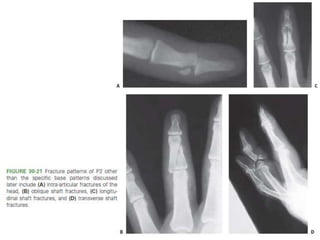

Middle Phalanx (P2) Fractures

• head, neck, shaft, and base.